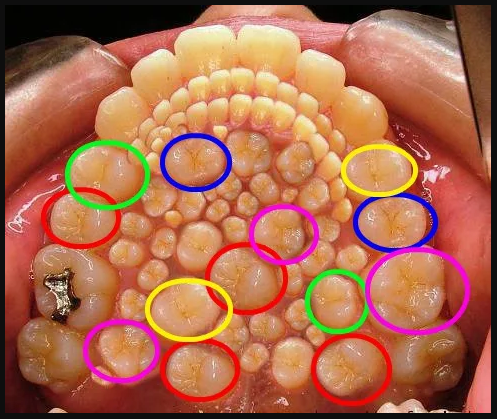

La foto di un caso di iperdontia su internet

Su internet sta girando una fotografia che mostrerebbe la bocca di un adulto sofferente di iperdontia. Si tratta di una foto che circola da diversi anni: l’iperdontia è una condizione medica in cui le persone affette presentano un numero eccessivo di denti.

Nel febbraio 2019 la pagina Facebook “Pictures From History” ha rinnovato l’interesse per questa immagine quando l’hanno condivisa sui social media con la didascalia “Dentro la bocca di un adulto che soffre di iperdontia”.

Tuttavia, come ci informa Snopes, la fotografia virale vista qui non è un’immagine reale della bocca di una persona che sta vivendo quella condizione.

Questa immagine è online dal dicembre 2010, quando è stata condivisa sul blog Holyloly. L’immagine ha raggiunto un pubblico più vasto pochi mesi dopo quando è stata inclusa in un post dalla SCP Foundation – un’organizzazione fittizia che pretende di coprire una vasta gamma di materiali altamente classificati – in un post del blog su SCP-478, una malattia immaginaria che fa sì che un corpo generi denti extra:

È comunque chiaro che questa immagine è stata creata con l’aiuto del software di fotoritocco digitale. Sembra che qualcuno abbia scattato una fotografia autentica di una bocca e poi abbia duplicato molti dei suoi denti per far figurare che l’immagine catturasse un caso estremamente grave di iperdontia. Il ritocco è evidente quando si notano i denti ripetuti digitalmente in tutta l’immagine.